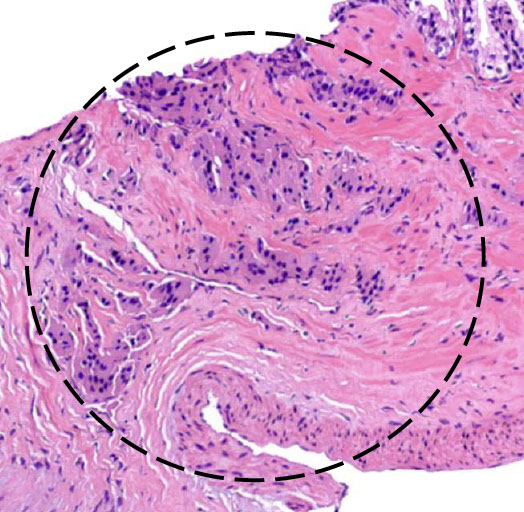

EXTRAPROSTATIC EXTENSION (EPE)

Tumor beyond confines of gland

• Admixed with periprostatic adipose tissue; easily recognized in posterolateral, posterior, lateral regions

• Tumor in skeletal muscle does NOT constitute EPE

• Extent ( nonfocal ) and location of EPE tshould be documented

staging pitfall - LASOP 2021

SEMINAL VESICLE INVASION

Tumor invades muscular wall of extraprostatic portion of seminal vesicles

SURGICAL MARGIN INVOLVEMENT (+SM)

• Tumor extends extraprostatic or intraprostatic) to prostate inked surface

• For +SM document:

- Location

- Extent (limited: <3 or non limited: ≥3 mm; linear length of SM)

- Gleason pattern @ +SM: pattern 3, 4, 5